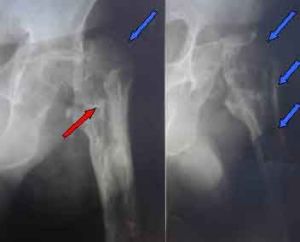

醫源性骨髓炎是一種廣義上的創傷性骨髓炎,近年來,人工假體、內固定架、骨水泥等的套用越來越廣,由於植入假體削弱了人體正常的防禦機制,或於由無菌操作不嚴格而引起骨組織發生感染。

與急性外傷性骨髓炎相似,病理特點是骨質破壞、壞死和反應性骨質增生同時存在,致病菌與各個醫院病菌檢出率有關。一般以金黃色葡萄球菌,溶血性鏈球菌,可能會存在厭氧菌。